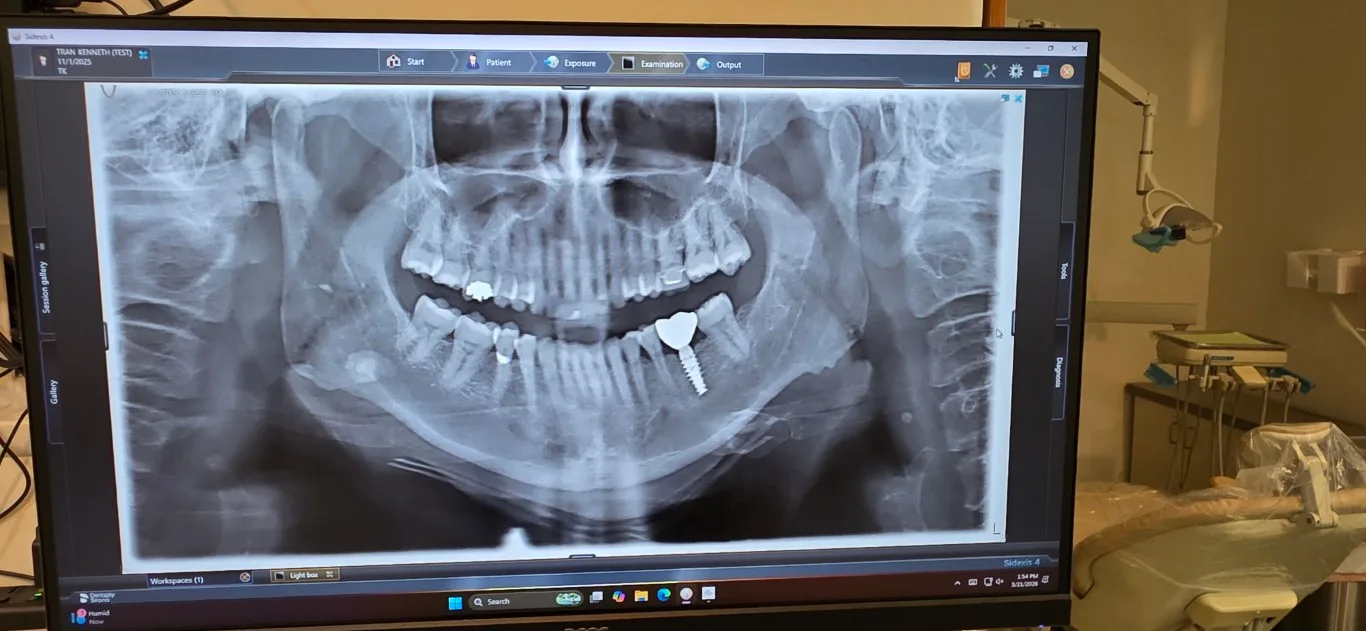

Digital X-ray showing dental implant placement at Peninsula Dentistry

Dental implants are titanium posts surgically placed into the jawbone to permanently replace missing teeth. Each implant supports a custom zirconia crown that looks, feels, and functions like a natural tooth. At Peninsula Dentistry in Huntington Beach, Dr. Tran has placed thousands of implants over his 20-year career using 3D imaging and digital planning for precise, long-lasting results.